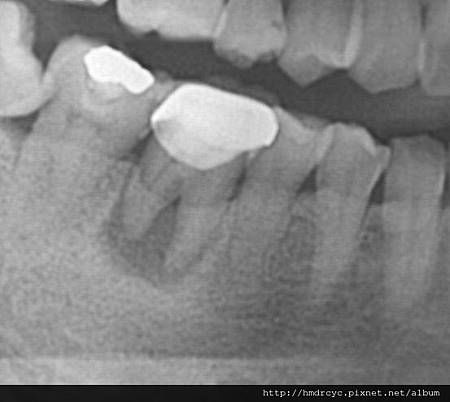

假牙必須利用X光片來更精確的判斷有沒有問題

在X光上面假牙是白色的影像

但X光片判讀困難 所以這部分必須仰賴醫師的專業

通常假牙底下牙齒會有幾個問題

比較難從外部檢查 而建議做X光片檢查

包括: